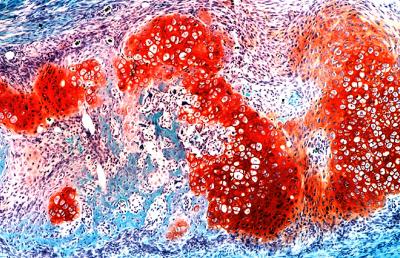

One of these key cell types is a small population of "messenger" cells, which can be identified by the activity of a gene called Sox9. These messenger cells reside in the sheath of tissue, called the periosteum, which surrounds each rib. Upon injury, a protein called "Hedgehog" activates the messenger cells, which in turn tell neighboring cells to differentiate into a hybrid between cartilage and bone. These hybrid cells form the "repair callus" that converts into newly regenerating bone.

The scientists also noted that while hybrid bone-cartilage cells play a critical role in regenerating injured ribs, they are surprisingly absent while the ribs originally form during embryonic development. This calls into question an existing dogma in many biology textbooks: that regeneration is a recapitulation of development. Instead, regeneration and repair may be their own distinct processes, involving unique cell types and genetic programs.